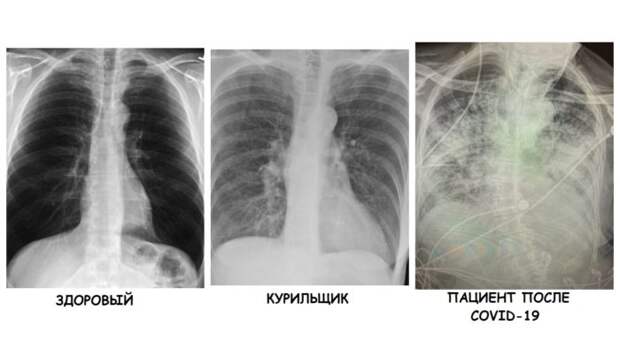

Снимок грудной клетки здорового ребенка: примеры и диагностика